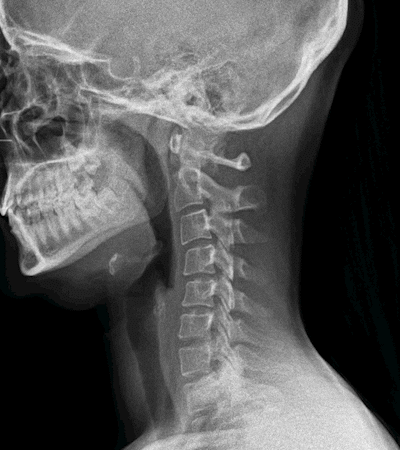

La radiología digital dinámica permite ver la anatomía del paciente en movimiento

La radiología digital dinámica (Dynamic Digital Radiography -DDR, por sus siglas en inglés) es una innovadora tecnología de rayos X que permite obtener series de imágenes digitales en la que se aprecia la anatomía en movimiento. "El equipo, emite 15 pulsos por segundo durante un tiempo de exposición de 15 segundos, lo que ofrece una imagen dinámica de la anatomía del paciente de forma muy rápida", explica el Dr. Vicente Martínez de Vega

, jefe del Servicio de Diagnóstico por la Imagen del Hospital Universitario Quirónsalud Madrid, que dispone del primer equipo portátil en Europa de estas características. Este equipamiento de la empresa Konica Minolta ofrece a los radiólogos la posibilidad de capturar y analizar el movimiento fisiológico de una estructura corporal con una dosis muy inferior a un estudio por fluoroscopia.

"La radiología digital dinámica tiene utilidad en los estudios ortopédicos en los que se aprecia una imagen radiográfica del movimiento de las articulaciones como la muñeca, el hombro o la rodilla. También tiene gran utilidad para estudiar la columna en flexión y extensión. Nos ofrece una visión muy completa del movimiento de la articulación", explica el Dr. Martínez de Vega, que también cree que esta nueva tecnología tiene otro punto fuerte en los estudios de función pulmonar: "Puede tomar imágenes de dos o tres respiraciones completas del paciente y mostrarnos una imagen en movimiento en el que se visualiza con claridad cómo se llenan y vacían los pulmones y el movimiento del diafragma. Se aprecia si existen adherencias pleurales o si hay zonas que no ventilan correctamente. A la información visual del cineloop (imágenes en secuencia), se pueden añadir mapas de ventilación y del movimiento realizados gracias a softwares avanzados específicos de la estación de trabajo, que analizan las diferentes densidades del pulmón y ofrecen al radiólogo datos cuantificables de función pulmonar". Según el Dr. Martínez de Vega, esta información es muy útil en las Unidades de Cuidados Intensivos en los que ayudará a valorar más adecuadamente la evolución de los pacientes desde el punto de vista cardiopulmonar. Otra gran ventaja de este equipo es que es portátil, lo que permite realizar los estudios a pie de cama de los pacientes sin necesidad de desplazarlos.

"La radiación que recibe un paciente que se somete a una radiografía digital dinámica es similar a una placa postero-anterior y lateral de rayos X convencional, pero aporta mucha más información", detalla el Dr. Martínez de Vega, que afirma que la radiología digital dinámica ofrece una información nueva que no habíamos visto hasta ahora: "Hemos pasado de obtener información morfológica a información funcional y cuantificada".